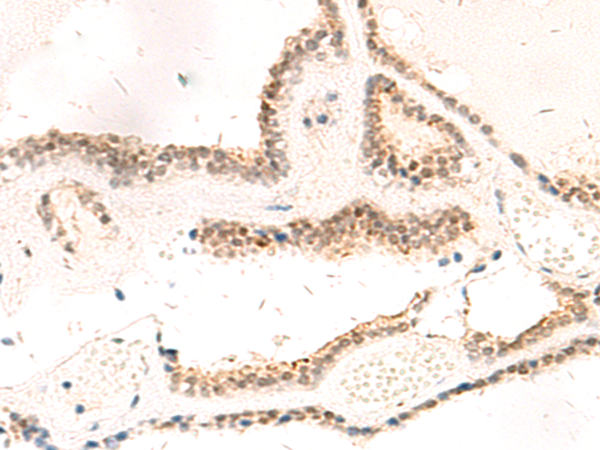

IHC positive control:

Human tonsil and Human thyroid cancer

IHC Recommend dilution:

50-300